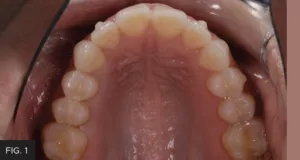

The following case shows a common clinical scenario. A patient presented with a food trap between two upper posterior teeth. Flossing in this area was difficult due to the floss shredding on the sharp edges of the restorations present on both teeth in the food trap. This had been present in the mouth for several years. (FIG. 1)

Pre-op: patient presented with a chief complaint of a food trap between long-standing composite restorations on teeth #12 and #13. Decay on the mesial of #13 was detected radiographically.

Clinically, teeth #s 12 and 13 displayed long, thin, flat, poorly contoured marginal ridges on the mesial of #13 and distal of #12, along with a small chip on the distal marginal ridge of #13. Radiographically, caries were detected on the gingival margins of the distal of #12 and the mesial of #13, respectively. These findings support the chief complaints of both food entrapment and difficulty in accessing interproximal for flossing. Robust, rounded marginal ridges, contoured from buccal to lingual, and from mesial to distal provide a strong surface to keep food cycling through the masticatory process and protect the integrity of the contact. Additionally, this smooth rounded marginal ridge helps the dental floss easily access the interproximal area. With this in mind, the treatment plan involved the removal and replacement of new Class II restorations on teeth #12 and #13 with improved, natural contours and contacts that would resist trapping food and be more amenable to the patient’s oral hygiene care. The patient had a low dental anxiety index and, given the age of the restorations and the frustration with consistently trapping food and breaking floss, readily agreed to treatment.